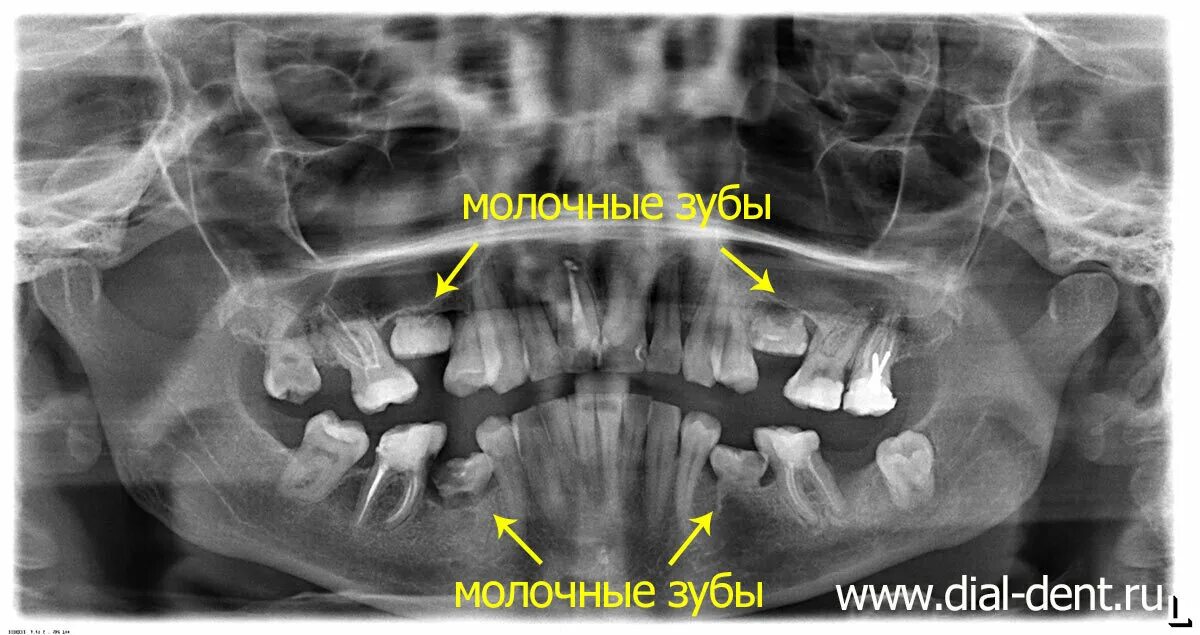

У ребенка нет зачатка постоянного зуба